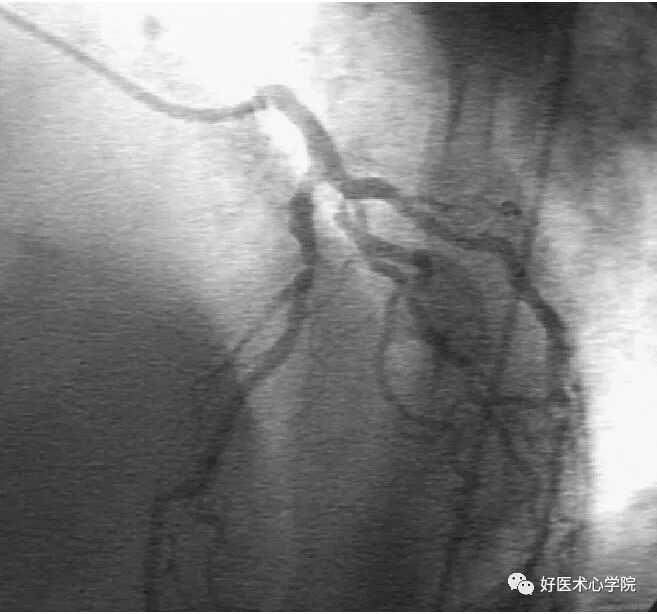

右前斜位:观察右冠近中段的体位。

造影导丝是什么珍藏 冠脉造影从流程到诊断,基础必备!_https://www.jmylbn.com_新闻资讯_第55张